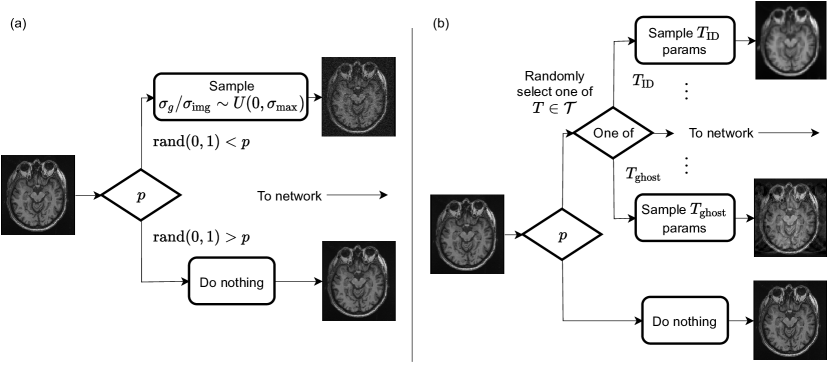

Refer to caption

Figure 9: Data augmentation schemes using (a) single and (b) multiple augmentation transforms. Transforms were applied with probability p𝑝p for each sample loaded during training. Transform parameters were sampled uniformly between the parameter value that constitutes no transformation (e.g., zero in the case of noise) and the parameter value constituting the maximum intensity of transformation desired. In the case of multiple transforms, one transform is randomly selected (with equal probability) each time augmentation is applied.

In this experiment, we investigated whether simple augmentation strategies can eliminate most of the sensitivities observed in Section 3.1, without modifications to network architecture. We started by augmenting training samples using a single transform, as shown in Figure 9a (see Section 2.4 for training details). First, we studied if simply providing mildly (i.e., low-severity) transformed inputs to the network was enough to develop robustness to a particular transform across severity levels, or whether the intensity range of the augmentation transform applied during training had an effect on robustness at test time. As another key complementary variable in the augmentation scheme, we studied the frequency p𝑝p with which transforms were applied to the training data, and how this parameter affects robustness for varying degrees of transform intensity seen by the model through data augmentation. Second, we studied whether augmentation with a single transform can improve robustness to other transforms. We started by training the baseline U-Net studied in Section 3.1 using MRI noise as an augmentation transform, with varying probabilities of transformation during training, p𝑝p, and with varying intensity ranges of noise supplied to the network during training. Intensity was controlled by sampling σg/σimgU(0,σmax)similar-tosubscript𝜎𝑔subscript𝜎img𝑈0subscript𝜎max\sigma_{g}/\sigma_{\mathrm{img}}\sim U(0,\sigma_{\mathrm{max}}) uniquely for each newly loaded training sample, where σmaxsubscript𝜎max\sigma_{\mathrm{max}} controls the maximum intensity of noise applied to the image relative to the image intensity standard deviation. Models were trained with σmax{0.16,0.32,0.48,0.64,0.80}subscript𝜎max0.160.320.480.640.80\sigma_{\mathrm{max}}\in\{0.16,0.32,0.48,0.64,0.80\}, corresponding to the noise severity levels in the benchmarking test sets.

3.3.2 Augmentation with multiple transforms

Next, we extended the experiments from Section 3.3.1 to include all transforms studied in this work during augmentation. The augmentation scheme corresponding to this experiment is illustrated in Figure 9b. Instead of applying the same transform every time with probability p𝑝p (albeit with varying degrees of intensity), the probability p𝑝p indicates the frequency with which a transform will be applied at all. Once the algorithm is triggered to apply a transform during training, one of the 11 transforms is randomly selected (with equal probability for each transform); then, parameters controlling the intensity of the transform are sampled and the transform is applied to the input image. Transform parameters were sampled uniformly for all transforms, ranging from the parameter value that corresponds to no transformation (e.g., σg/σimg=0subscript𝜎𝑔subscript𝜎img0\sigma_{g}/\sigma_{\mathrm{img}}=0 for noise) and the parameter value corresponding to the maximum severity level in our benchmarking test sets. With the transform intensity range fixed (based on results from Section 3.3.1), the only parameter we varied in this experiment was the augmentation probability p𝑝p. We studied whether larger probabilities p𝑝p would be required to attain the same degree of robustness on the single transform we studied in Section 3.3.1, given the fact that more distinct transforms are now being applied with the same overall augmentation frequency. In addition, we investigated the robustness improvement achieved towards all transforms by employing this combined augmentation strategy.